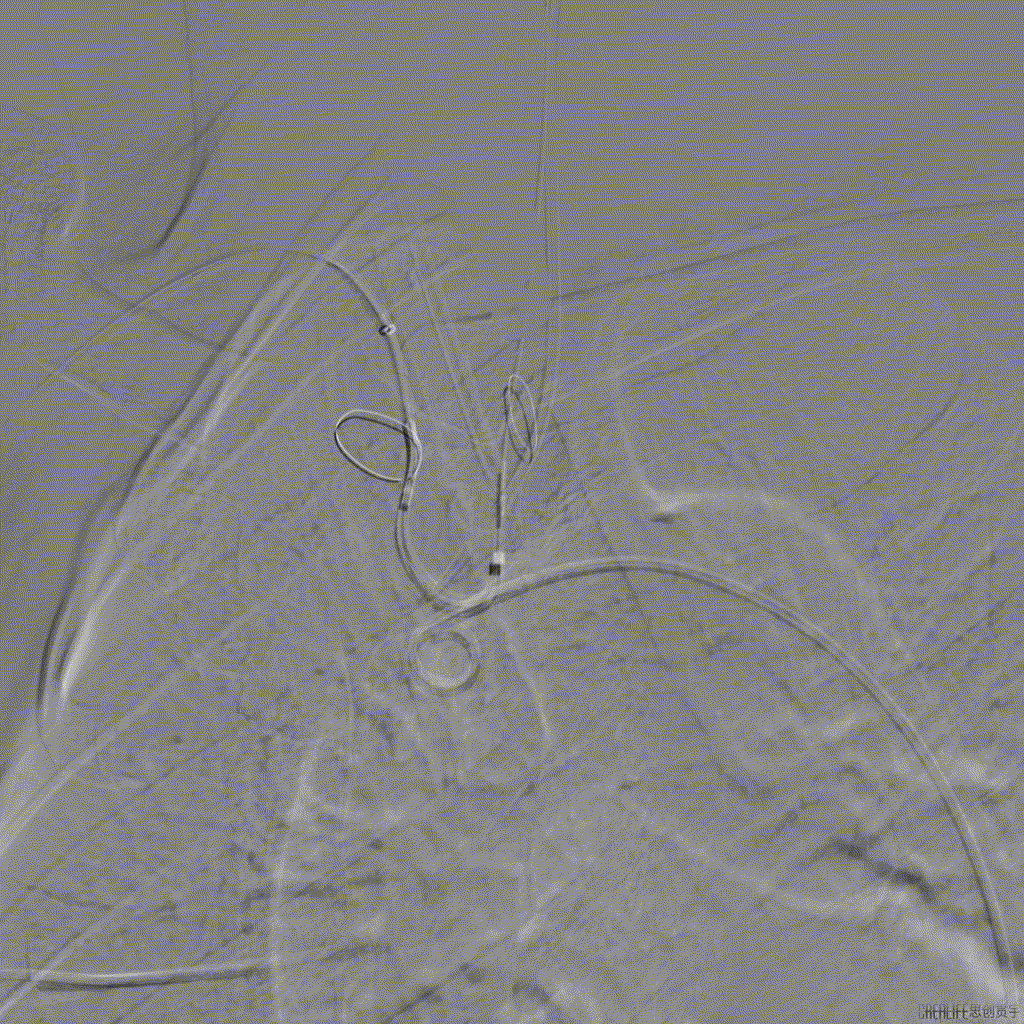

术中DSA影像

张小卫教授在SENTINEL成功应用后表示:脑卒中是所有结构手术中一直非常头疼的问题,目前阶段会优先考虑在高龄,动脉硬化严重的TAVR以及二尖瓣狭窄患者中应用SENTINEL抗栓塞脑保护装置,其通过性和容忍度都非常优秀。该例患者虽然解剖复杂困难,但是整个操作相对简单仅用时3min即顺利成功植入,并且捕获到血栓,对于结构手术的安全保护作用意义深远。